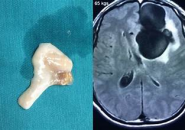

Giun đũa chó mèo này sẽ đẻ trứng, trứng theo phân ra ngoài môi trường và sau 1-2 tuần lễ các trứng này sẽ hoá phôi ,tiếp theo các ấu trùng giun đi xuyên qua thành ruột và theo đường máu di chuyển đến gan, phổi, hệ thần kinh trung ương .

Phần lớn người bệnh nhiễm ấu trùng giun đũa chó mèo không có triệu chứng lâm sàng và các ký sinh trùng thường chết trong vòng một vài tháng. Tuy nhiên, một số trường hợp có biểu hiện triệu chứng nhẹ như: